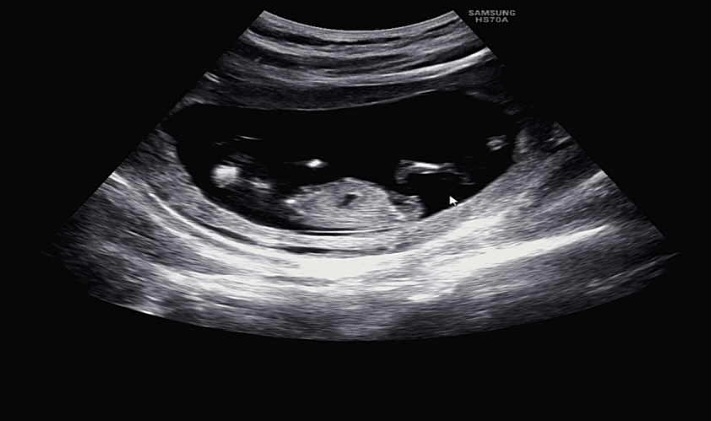

성별 보는법 도저히 알수가없네요🥲

왼쪽이머리고..오른쪽은 다리라는데.. 어때보여요?? 전 아무리봐도 모르겠어요ㅜㅜㅋ

약간 애매하긴 하지만 딸같아용 ㅎㅎ